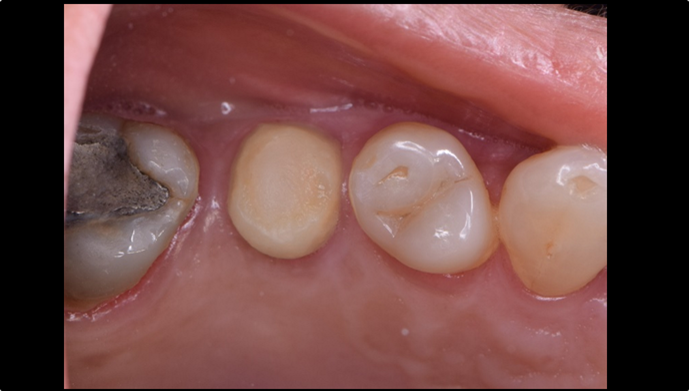

Clinical case: Immediate implant placement using R2GATE Guide & custom healing abutment

- Courtesy of Dr. Sam Omar, Egypt -

Keywords

Dr. Dr. Sam Omar,Digital Guided Surgery,Digital Digital Guided Surgery,Digital ONE-DAY Implant,Maxillary Posterior,#16,Guided surgery,Loading,Flapless,AnyRidge,R2GATE,MEGA ISQ,R2GATE Full surgical kit